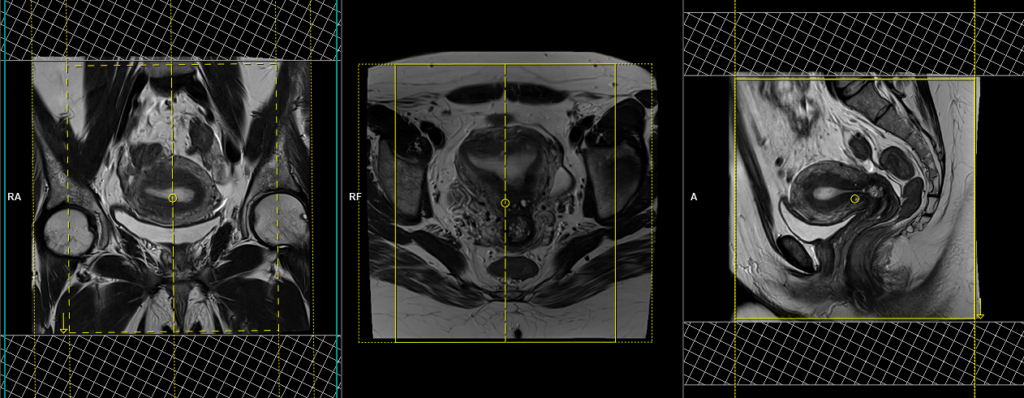

T1 tse fat sat axial oblique 3mm SFOV of uterus

Plan the axial oblique slices on the sagittal plane; angle the position block perpendicular to the endometrium (this angulation can be vary according to the pathology check the normal variation section for the differences in planning). Check the positioning block in the other two planes. An appropriate angle must be given in the coronal plane (perpendicular to the endometrium). Slices must be sufficient to cover the whole uterus and ovaries. Adding saturation bands on top and front of the axial block will reduce artifacts from arterial pulsation and breathing.

Parameters

TR 400-600 | TE 15-25 | SLICE 3 MM | FLIP 130 | PHASE R>L | MATRIX 256X256 | FOV 180-230 | GAP 10% | NEX(AVRAGE) 3 |

T1 VIBE DIXON 3D sagittal dynamic 1 pre 8 post

Plan the sagittal 3D block on the axial plane, angling the positioning block parallel to the endometrium. Check the positioning block in the other two planes. An appropriate angle must be given in the coronal plane (perpendicular to the uterus). Slices must be sufficient to cover the entire pelvis from the right acetabulum to the left acetabulum. The field of view (FOV) must be large enough to encompass the entire pelvis (usually 270mm-300mm). Adding saturation bands on the top and front of the sagittal block will reduce artifacts caused by arterial pulsation and breathing. Ensure an adequate level of slice and phase oversampling to prevent any wrap-around artifacts.

TR 4-5 | TE 2-3 | FLIP 10 | NEX 1 | SLICE 2 MM | MATRIX 256X256 | FOV 200-250 | PHASE R>L | DYNAMIC 9 SCANS | IPAT ON |